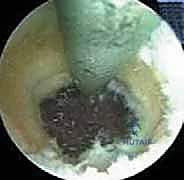

3. الاستكشاف التشخيصي بالمنظار:

يتم إدخال كاميرا المنظار عالية الدقة. يقوم الدكتور هطيف بإجراء فحص شامل وفحص ديناميكي للمفصل من الداخل، لتقييم حالة الغضاريف، البحث عن الأجسام الحرة (Loose bodies) الناتجة عن تفتت العظام، وتقييم حجم النتوءات العظمية في الناتئ المرفقي.

4. إزالة النتوءات العظمية (Osteophyte Excision):

هذه هي الخطوة الأكثر دقة وحساسية، وهنا تتجلى خبرة الأستاذ الدكتور محمد هطيف. باستخدام أدوات دقيقة (Burr)، يقوم بنحت وإزالة النتوءات العظمية الخلفية التي تسبب الانحشار.

تحذير جراحي هام: يؤكد الدكتور هطيف دائماً على قاعدة جراحية ذهبية في هذه العملية: "يجب إزالة العظام الزائدة فقط (النتوءات)، ويجب عدم المبالغة في إزالة جزء من العظم الأصلي للناتئ المرفقي". لماذا؟ لأن الإفراط في إزالة العظم سيؤدي إلى فقدان المفصل لاستقراره العظمي، مما يضع ضغطاً مضاعفاً ومميتاً على الرباط الجانبي الزندي (UCL)، وقد يؤدي إلى تمزقه بالكامل لاحقاً. هذه الدقة في تحديد "كمية العظم المزال" هي ما يميز الجراح الخبير عن غيره.

5. تنظيف المفصل والإغلاق:

بعد التأكد من إزالة كافة العوائق العظمية واستعادة مدى الحركة الكامل (Extension) أثناء وجود المريض تحت التخدير، يتم غسل المفصل جيداً بسائل معقم لإزالة أي بقايا دقيقة. تُغلق الشقوق الصغيرة بغرزة واحدة لكل شق، وتُوضع ضمادة ضاغطة خفيفة.